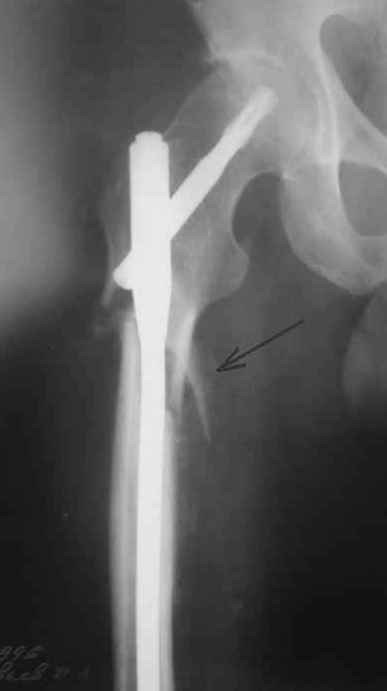

На операции я оставил осколок в области приводящих мышц бедра (ни пальпаторно, ни спицей сдвинуть не смог, "заклинило" насмерть). Фото спустя 2 месяца после операции (PFN). Только сейчас пациент стал более или менее активным. Сразу после операции жалобы на сильные боли при отведении и приведении бедра в области отломка. Сейчас отломок пальпируется и пациент испытывает дискомфорт, хотя амплитуда движений объективно прогрессирует.

Теперь думаю, надо все-таки было через минидоступ или резецировать, либо репонировать. Обычно при таких операциях уже на 2-й день пациенты на костыли и по отделению, а у этого задержка длительная получилась. Только спустя 2 недели кое-как на костыли взобрался. Ни отека, никакой неврологии, только эти боли в области осколка.